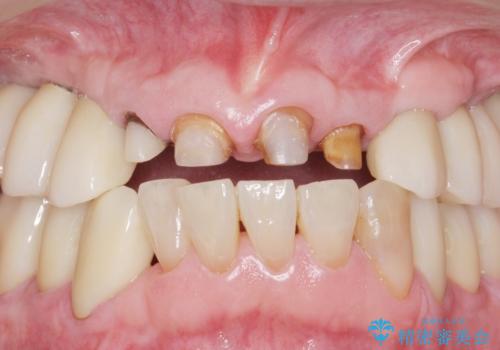

- 前歯の被せ物がとれたまま放置されていた患者様です。

前歯4本のうち3本の被せ物が脱離し、残りの1本の被せ物は劣化し変色していました。

古い被せ物や土台・虫歯をしっかり除去したのち、セラミック治療を行いました。